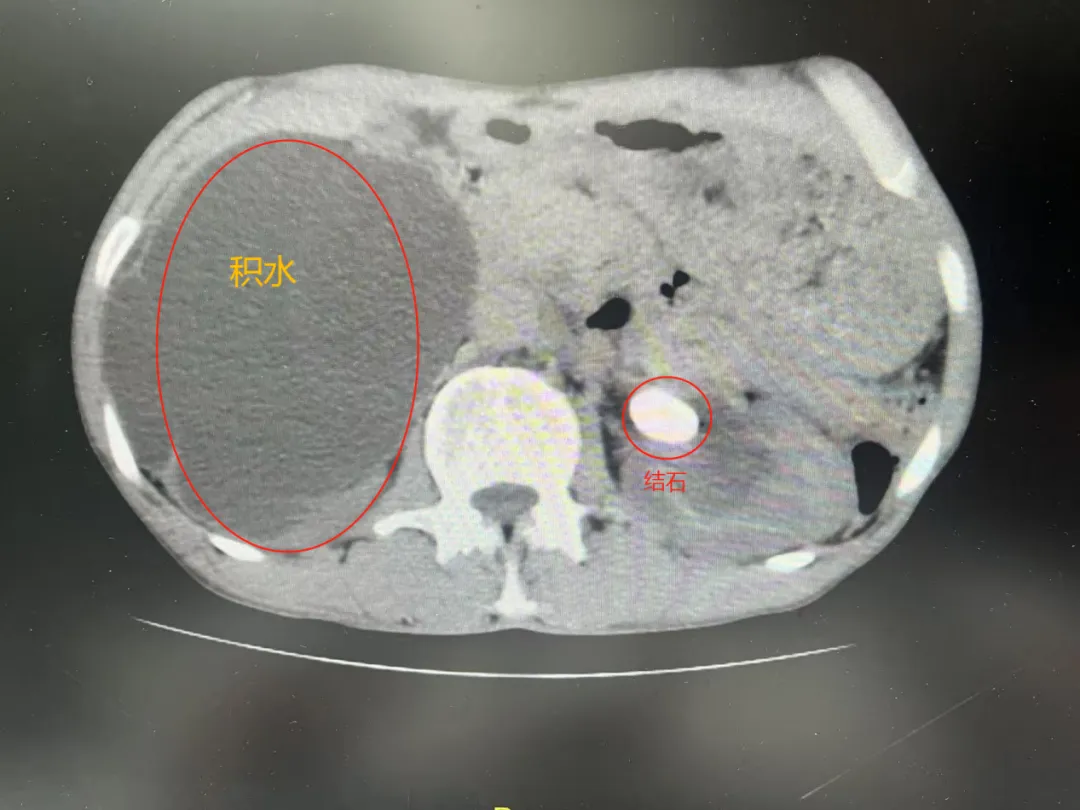

患者沙某,60岁,男性,因“反复腰腹部疼痛3年余,再发伴腹胀10天”入院,既往曾有“泌尿系结石”开放手术史。患者入院后完善CT检查提示1、右侧肾盂-输尿管移行处结石,大小约18*13*20mm,右肾体积增大,肾盂、肾盏明显扩张积液,肾皮质变薄2、左侧肾盂-输尿管移行处结石,大小约22*14*24mm,左肾形态饱满,肾盂、肾盏扩张积液。

次日复查泌尿系CT示:左侧肾盂-输尿管移行处结石已完全清除,未见肾脏积液及血肿达到了一次彻底清石的效果。目前,患者正在康复治疗中。